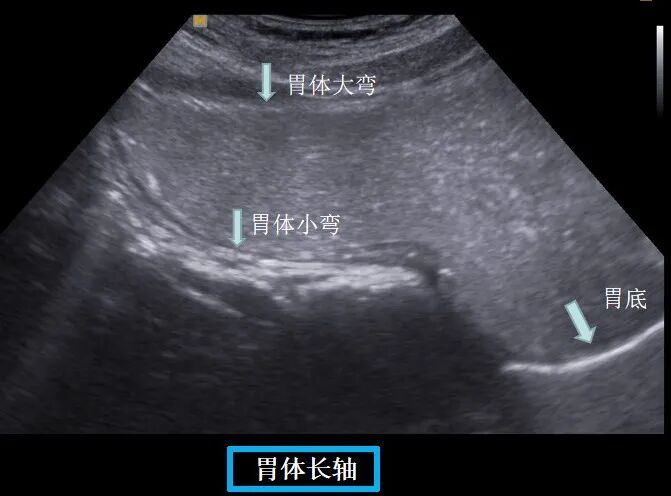

▲口服助影剂充盈后可清晰显示胃内结构